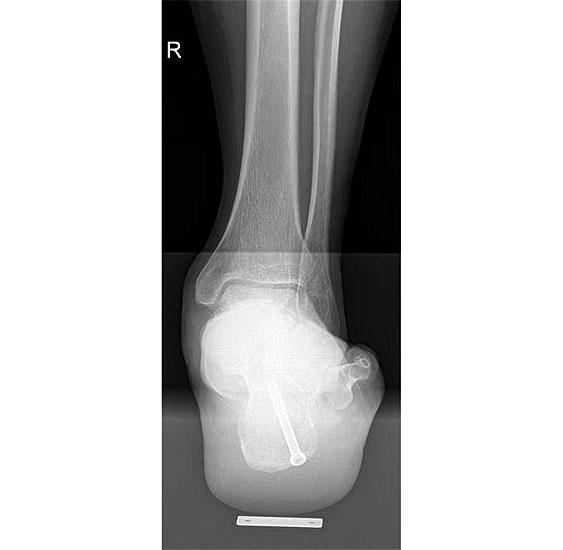

Abbildung Nr. 1: Röntgen Fuß: dp und seitlich stehend.

715.<br> Für die medialisierende Calcaneusosteotomie wird ein bogenförmiger Hautschnitt in Höhe des hinteren Fersenbeines gesetzt, die Subcutis bis zum Fersenbein durchtrennt und dieser bogenförmige Lappen nach ventral präpariert. Dadurch kommt es zu einem Schutz des Nervus suralis, welcher gemeinsam mit den Peronealsehnen nach vorne gehalten wird.<br> Es wird nun das Fersenbein mit einem Wundspreizer eingestellt und cranial sowie caudal mit 2 Hohmannhaken umfahren.<br> Dann wird das Fersenbein mit der oszillierenden Säge osteotomiert, mit dem Meißel und dem Wundspreizer distrahiert.<br> Danach wird das Fersenbein ca. 1 cm nach medial verschoben, unter Vermeidung der Cranialisierung des hinteren Calcaneus . Dann wird von dorsal über eine Hautstichincision der Bohrdraht für die 4,5mm (- 6,5 mm) kanülierte Schraube eingebracht und über die Osteotomie in den vorderen Calcaneusanteil vorgeschoben.<br> Kontrolle im Bildwandler in 2 Ebenen. Wenn die Bohrdrahtlage gut ist Überbohren für die kanülierten Schrauben und Eindrehen der Schraube. (Alternativ kann an Stelle der Schraubentechnik auch eine Fixation mit Stufenplatten oder Ähnlichem verwendet werden).<br> Wundverschluss am lateralen Zugang und über der Stichincision.</p>"> 715.<br> Für die medialisierende Calcaneusosteotomie wird ein bogenförmiger Hautschnitt in Höhe des hinteren Fersenbeines gesetzt, die Subcutis bis zum Fersenbein durchtrennt und dieser bogenförmige Lappen nach ventral präpariert. Dadurch kommt es zu einem Schutz des Nervus suralis, welcher gemeinsam mit den Peronealsehnen nach vorne gehalten wird.<br> Es wird nun das Fersenbein mit einem Wundspreizer eingestellt und cranial sowie caudal mit 2 Hohmannhaken umfahren.<br> Dann wird das Fersenbein mit der oszillierenden Säge osteotomiert, mit dem Meißel und dem Wundspreizer distrahiert.<br> Danach wird das Fersenbein ca. 1 cm nach medial verschoben, unter Vermeidung der Cranialisierung des hinteren Calcaneus . Dann wird von dorsal über eine Hautstichincision der Bohrdraht für die 4,5mm (- 6,5 mm) kanülierte Schraube eingebracht und über die Osteotomie in den vorderen Calcaneusanteil vorgeschoben.<br> Kontrolle im Bildwandler in 2 Ebenen. Wenn die Bohrdrahtlage gut ist Überbohren für die kanülierten Schrauben und Eindrehen der Schraube. (Alternativ kann an Stelle der Schraubentechnik auch eine Fixation mit Stufenplatten oder Ähnlichem verwendet werden).<br> Wundverschluss am lateralen Zugang und über der Stichincision.</p>" srcset="/assets/images/a/3-raswd6qgkh6s353.jpg 1x, /assets/images/g/3-exngvjjv83x827d.jpg 1.5x, /assets/images/w/3-836r57qt8j3eh0w.jpg 2x" width="270" height="240" loading="lazy">

Abbildung 3

Abbildung 4